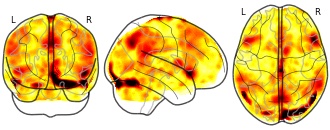

oliver.xie's temporary collection: pmap_L

EmailClick to copy linkLink copied Cite(2023). oliver.xie's temporary collection: pmap_L [Dataset]. http://identifiers.org/neurovault.image:802572niftiAvailable download formatsUnique identifierhttps://identifiers.org/neurovault.image:802572Dataset updatedAug 21, 2023License

Cite(2023). oliver.xie's temporary collection: pmap_L [Dataset]. http://identifiers.org/neurovault.image:802572niftiAvailable download formatsUnique identifierhttps://identifiers.org/neurovault.image:802572Dataset updatedAug 21, 2023LicenseCC0 1.0 Universal Public Domain Dedicationhttps://creativecommons.org/publicdomain/zero/1.0/

License information was derived automaticallyDescriptionCollection description

None

Subject species

homo sapiens

Modality

fMRI-BOLD

Cognitive paradigm (task)

rest eyes open

Map type

Z

- Z